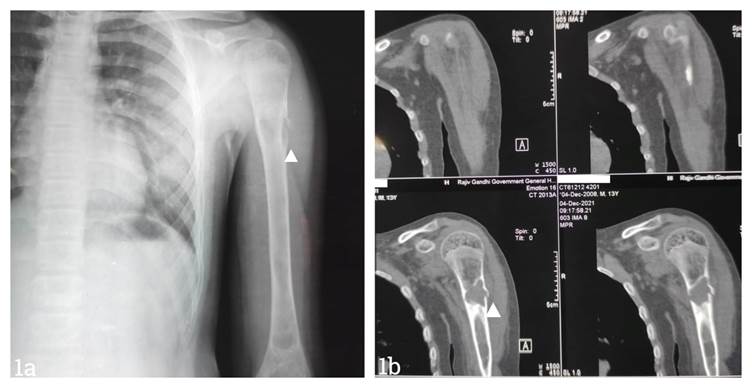

Fig 1a. X-ray showing a proximal fracture in the left humerus. Fig 1b. CT scan of the left shoulder showing a solitary bone cyst in the left humerus.

X-ray revealed a simple bone cyst in the left proximal humerus with a pathological fracture and a united right proximal humerus fracture. USG screening of the left shoulder revealed a solitary bone cyst.

CT scan of the left shoulder had a unilocular loculated central lytic expansile lesion with endosteal scalloping involving the diaphysis of the proximal humerus and a transverse fracture at the site of the lesion, with a thin, detached fracture fragment within the lesion and minimal solid periosteal reaction, suggestive of a solitary bone cyst complicated by fracture. The fracture was managed conservatively with a U slab. No other procedure was performed due to the risk of bleeding manifestations. His pain reduced, and there was no bleeding. Normal callus formation was observed in the X-ray after four weeks of management.